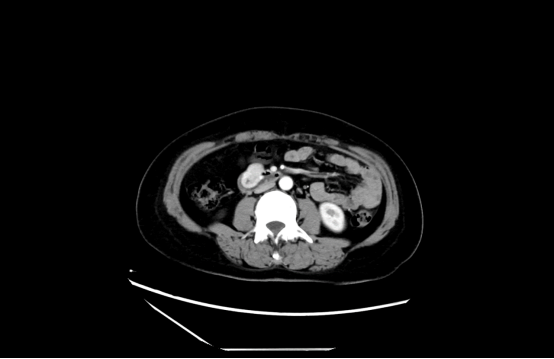

增强CT提示:十二指肠水平段见大小约2.6cm*2.1cm软组织块,向腔外膨胀性生长,边界清楚,增强动脉期明显强化,门脉期强化减弱,十二指肠管腔稍狭窄改变。一般来说,2cm及以上的十二指肠包块均建议外科治疗。由于患者病变靠近十二指肠乳头,外科手术需要做胰十二指肠根治术,该术式难度大、风险高、恢复期长,被称为外科手术中最具挑战性的手术之一。基于此,樊女士及家人对外科手术比较抗拒,希望通过内镜切除。